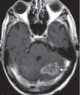

Esophageal metastasis